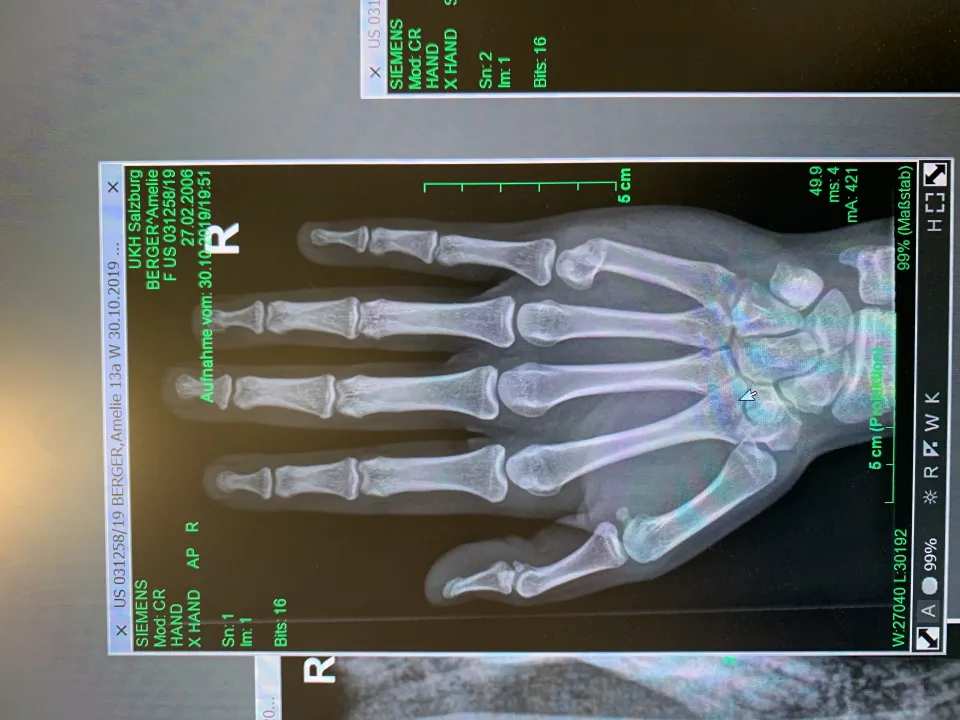

Leider hat sich unsere Power Amelie im letzten U14 Spiel verletzt. Sie hat sich die Hand gebrochen und muss jetzt 5 Wochen einen Gips tragen.